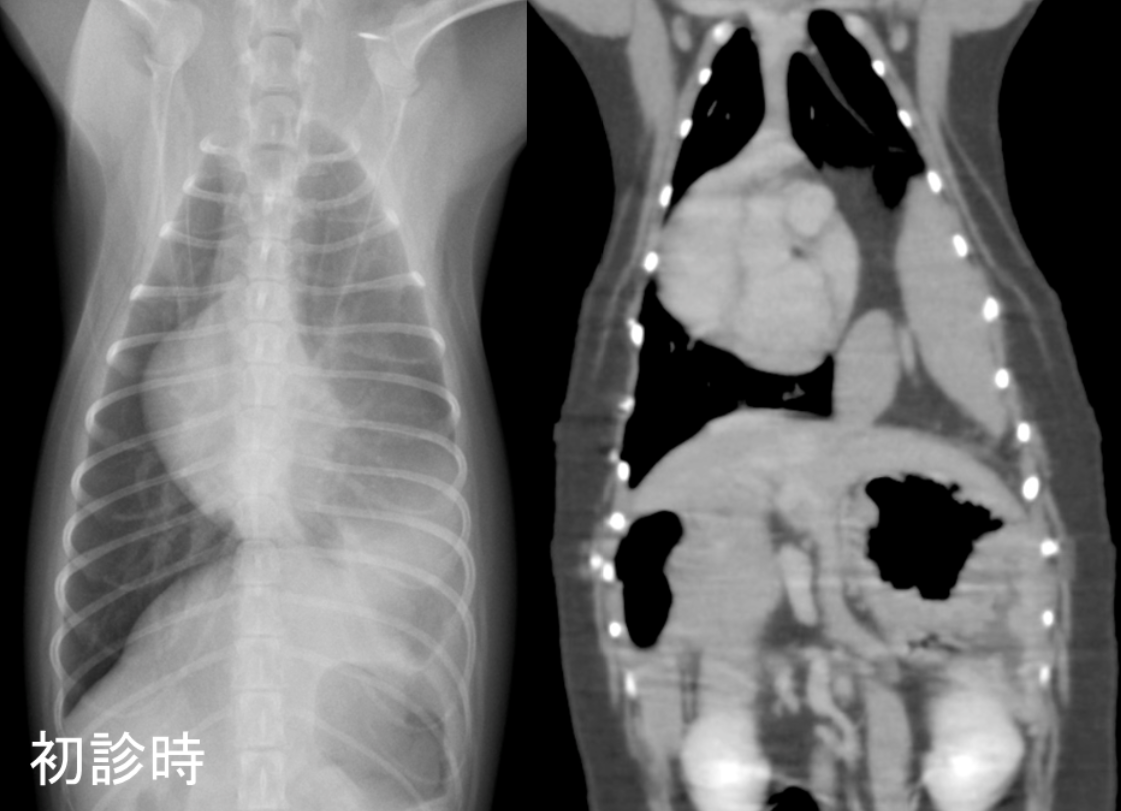

本人の状態や院内での身体検査、呼吸状態に異常は認められませんでしたが、麻酔前検査における胸部X線検査にて、左の肺に異常な白い領域が認められたため、後日CT検査を行いました。

CT検査においては、正常では横隔膜によって隔たれているはずの胸腔と腹腔のが連続しており、横隔膜左背側の孔からは左胸腔内へ脾臓が脱出していました。

初診時のレントゲン画像(左)、CT画像(右)